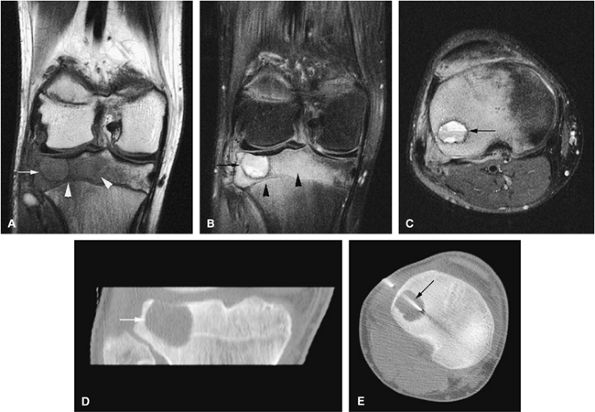

FIGURE 14-34 ● Extensive marrow edema (arrowheads) in reaction to an epiphyseal-based chondroblastoma of the tibia (arrows) demonstrates low signal intensity on a coronal T1-weighted image (A) and hyperintensity on a coronal STIR image (B). Axial STIR image (C) demonstrates fluid–fluid levels within the lesions (arrow). (D) A coronal CT image shows a well-defined lytic defect in the tibial plateau (arrow). (E) An axial CT image obtained during radiofrequency ablation of the tumor shows the radiofrequency probe (arrow) within the chondroblastoma.

Epiphyseal and metaphyseal marrow edema associated with periosteal reaction is a frequent finding, seen in up to 57% of cases of long-bone involvement.67 MR imaging is sensitive to this extensive reactive marrow edema, which demonstrates decreased signal intensity on T1-weighted images and increased signal intensity on T2-weighted or STIR images.

Fluid–fluid levels can be seen in chondroblastomas.53

T2-weighted images are useful in demonstrating the lobular chondroid internal architecture and fine lobular margins of the lesion.68